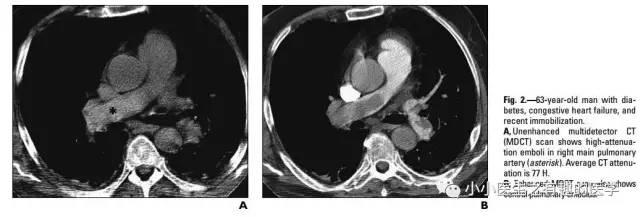

作者单位:Department of Radiology, Thoracic Imaging Section, San Francisco General Hospital。旧金山总医院。

如图,高密度影的那一条。不怕,有增强CT证实。

上面图片的英文原版: